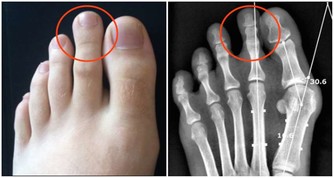

讀初中時,住校,許多同學出現了手上長小泡泡的情況,很癢,經常抓,也會出水,

就如以下這個圖,這即是濕氣太重的體現之一